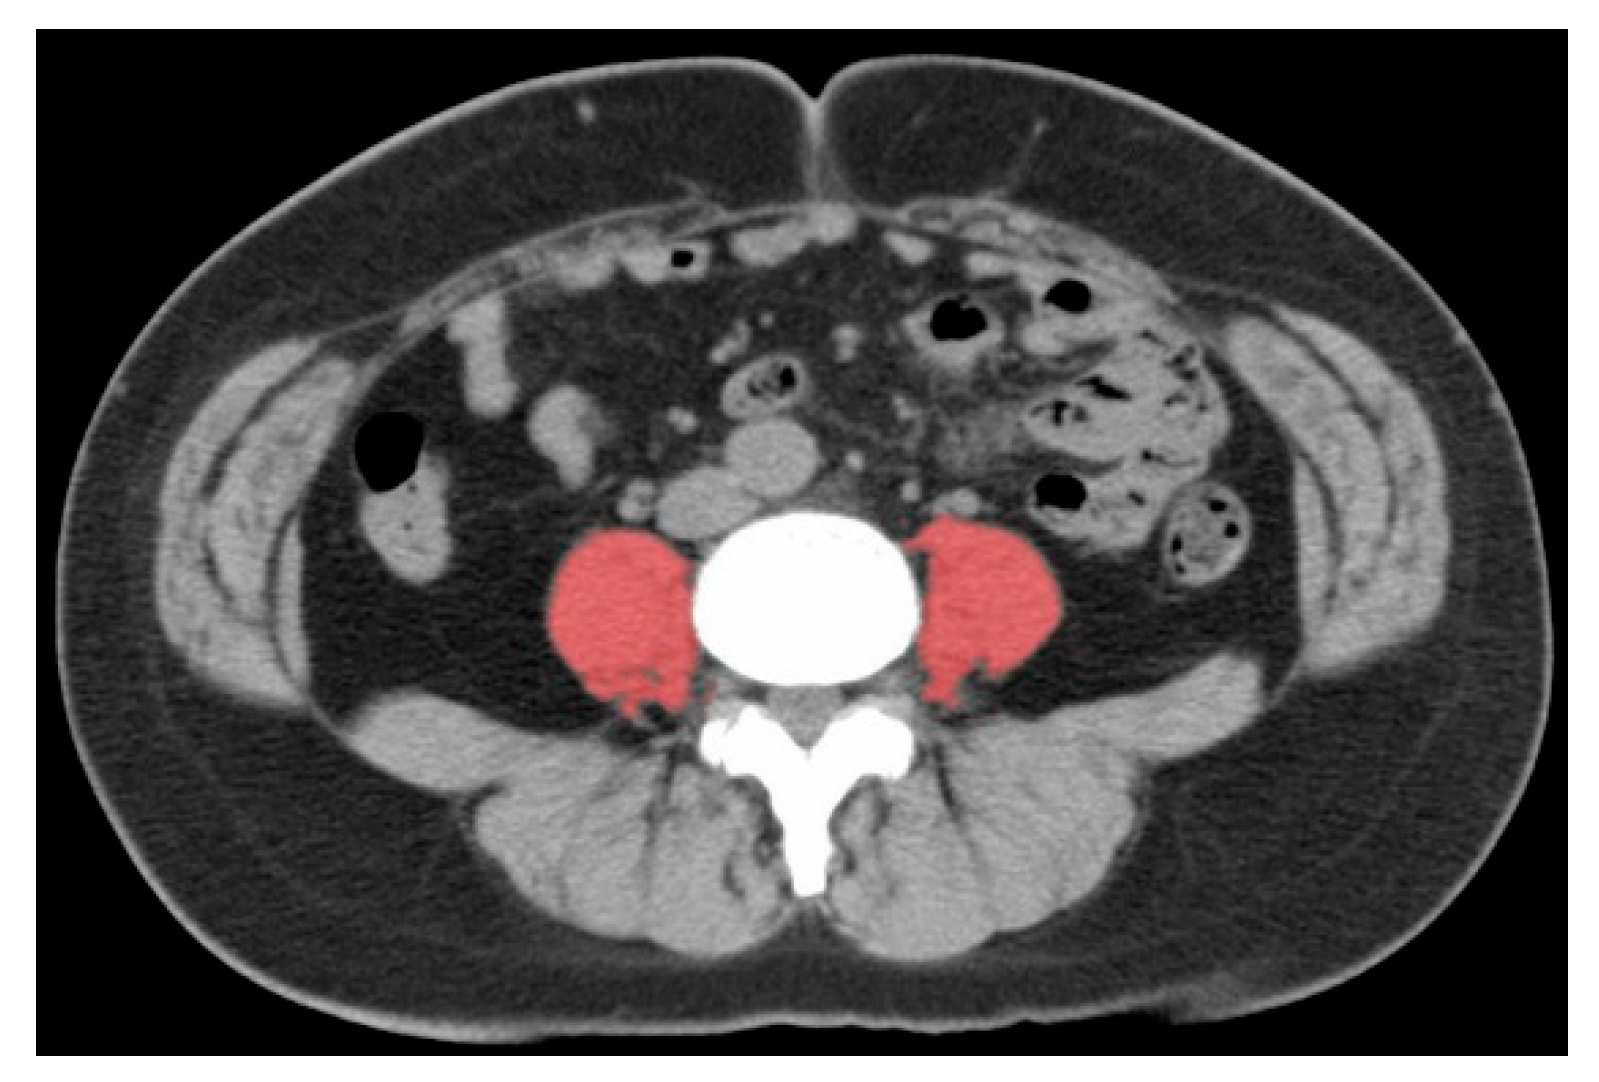

- Mitsiopoulos, N.; Baumgartner, R.N.; Heymsfield, S.B.; Lyons, W.; Gallagher, D.; Ross, R. Cadaver validation of skeletal muscle measurement by magnetic resonance imaging and computerized tomography. J. Appl. Physiol. 1998, 85, 115–122. [Google Scholar] [CrossRef] [PubMed]

- Hamaguchi, Y.; Kaido, T.; Okumura, S.; Kobayashi, A.; Hammad, A.; Tamai, Y.; Inagaki, N.; Uemoto, S. Proposal for new diagnostic criteria for low skeletal muscle mass based on computed tomography imaging in Asian adults. Nutrition 2016, 32, 1200–1205. [Google Scholar] [CrossRef] [PubMed]